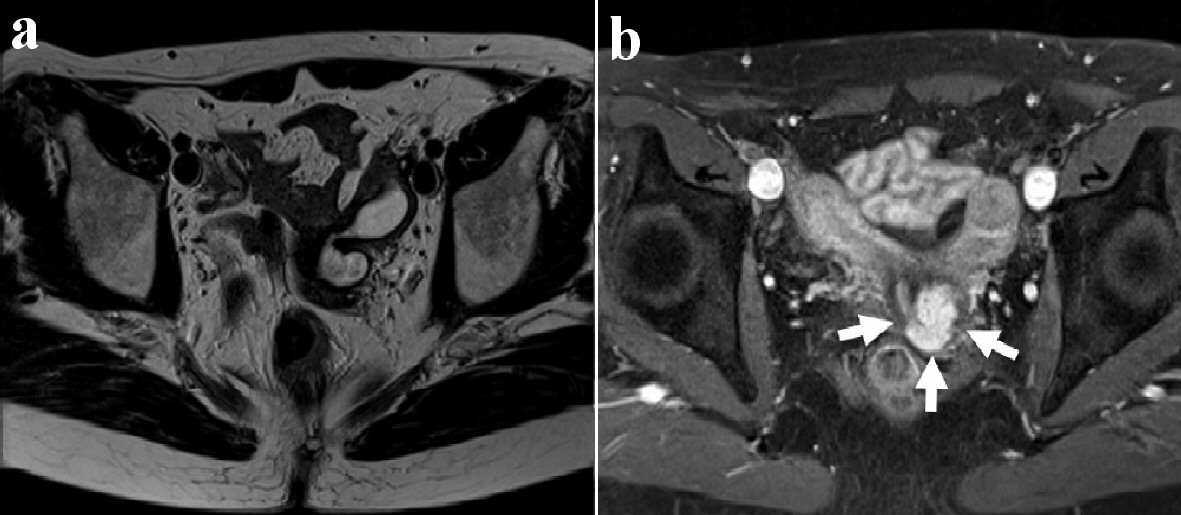

A 52-year-old nulligravida woman presented with 1 month of intermittent vaginal spotting 2 years after menopause. She had no history of smoking or medical diseases. Her family history included an uncle who died of gastric cancer. The patient had no history of in-utero diethylstilbestrol (DES) exposure. A previous cervical smear was unremarkable 11 months ago. Speculum examination revealed a single cervix and a 2-cm mass on the cervix, which showed macrocarcinoma of the cervix. No parametrial or vaginal involvement was detected. The biopsy specimen from the tumor on the uterine cervix revealed CCC. The tumor was comprised of atypical cells displaying enlarged nuclei with prominent nucleoli and clear-to-eosinophilic cytoplasm; the cells also displayed papillary structures with a hobnail-like appearance. Immunohistochemical staining showed that the tumor cells were positive for HNF-1β and napsin A. Laboratory data revealed that the patient’s squamous cell carcinoma antigens, carbohydrate antigen (CA) 125 levels, and CA19-9 levels were negative. Magnetic resonance imaging (MRI) of her pelvis showed uterine didelphys and a mass measuring 1.5 × 2.0 cm located in the left endocervix that had not invaded the parametria, adjacent organs, or regional lymph nodes. Furthermore, a left-sided obstructed hemivagina was observed (Fig. 1). Although an enhanced computed tomography (CT) scan of the chest and abdomen did not reveal evidence of lymph node metastasis or distant metastasis, left renal agenesis was observed (Fig. 2). Based on the findings of left renal agenesis, uterine didelphys, and obstructive hemivagina, we diagnosed her with OHVIRA syndrome and CCC of the cervix and classified her as International Federation of Gynecology and Obstetrics stage IB1.

![]() Click for large image | Figure 1. Axial view of pelvic magnetic resonance imaging (MRI). T2-weighted MR image shows the left obstructed hemivagina (a). T2-weighted postcontrast MR image shows uterine didelphys and a tumor measuring 1.0 × 2.0 cm on the left side of the uterine cervix (white arrows) (b). |